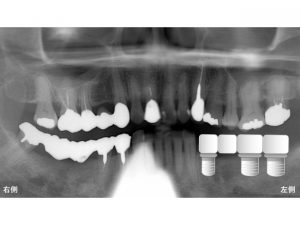

患者様は、下顎の左側奥歯に歯がないので噛めない

との主訴で来院されました。

欠損部を×印で記載します。

患者様は長い間左側奥歯が欠損していたため、

右側で噛むことが日常となっていました。

しかし、右側にブリッジが行ってあるのですが、

このブリッジごと、グラグラと動いてきました。

右側も噛めなくなり、困ってご来院となりました。

下顎左側の4歯欠損に対して、

3本のインプラントを埋入し、

4歯分の被せ物を作成するインプラントブリッジの治療計画を立てました。

以下はインプラント治療後です。